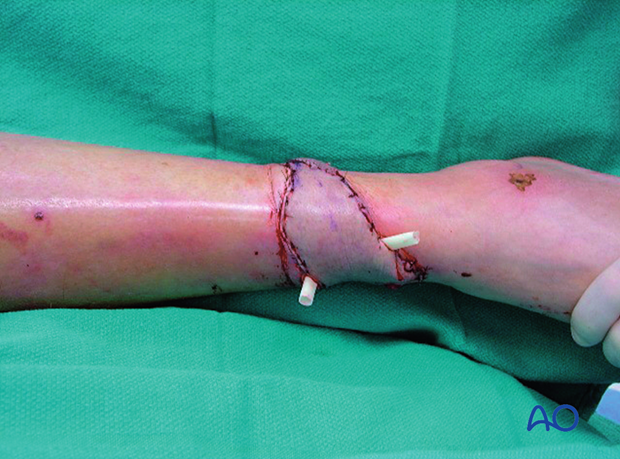

Locally administered antibiotics may have a supplementary role in the management of musculoskeletal infections. Particularly when the infected wound has poorly perfused areas, or “dead space”, antibiotic-laden cement is frequently used, both to fill the space and to deliver high doses of local antibiotic with low risk of systemic toxicity. A common technique is the use of antibiotic-laden polymethylmethacrylate (PMMA) beads.

Antibiotic-impregnated beads may be purchased in some countries (although they can be expensive) or made by the surgeon at a lower cost. One gram of cefazolin (a first-generation cephalosporin) or vancomycin is cheap and accessible. It is mixed with one standard package of PMMA and, as it hardens, beads of 5 mm are carefully wrapped around a non-absorbable heavy nylon stitch (see intraoperative photograph).

Tobramycin powder (1.2 g) may also be mixed with PMMA for broader-spectrum coverage.

Empty space (“dead space”) under tissue flaps, or within bony cavities, within the debrided wound allows re-accumulation of exudate and may become a reservoir of bacteria. Antibiotic levels may be low in this poorly perfused fluid accumulation. Filling this dead space in some way is an important part of wound management.

Treatment strategies for filling dead space include antibiotic beads or other temporary space fillers (calcium sulphate, bone cement, etc.). The wound itself should be covered to avoid desiccation or contamination. This can be done with an impermeable dressing (adherent plastic), or vacuum-assisted closure device, as illustrated. The latter, by applying sub-atmospheric pressure, reduces dead space volume in pliable tissues.